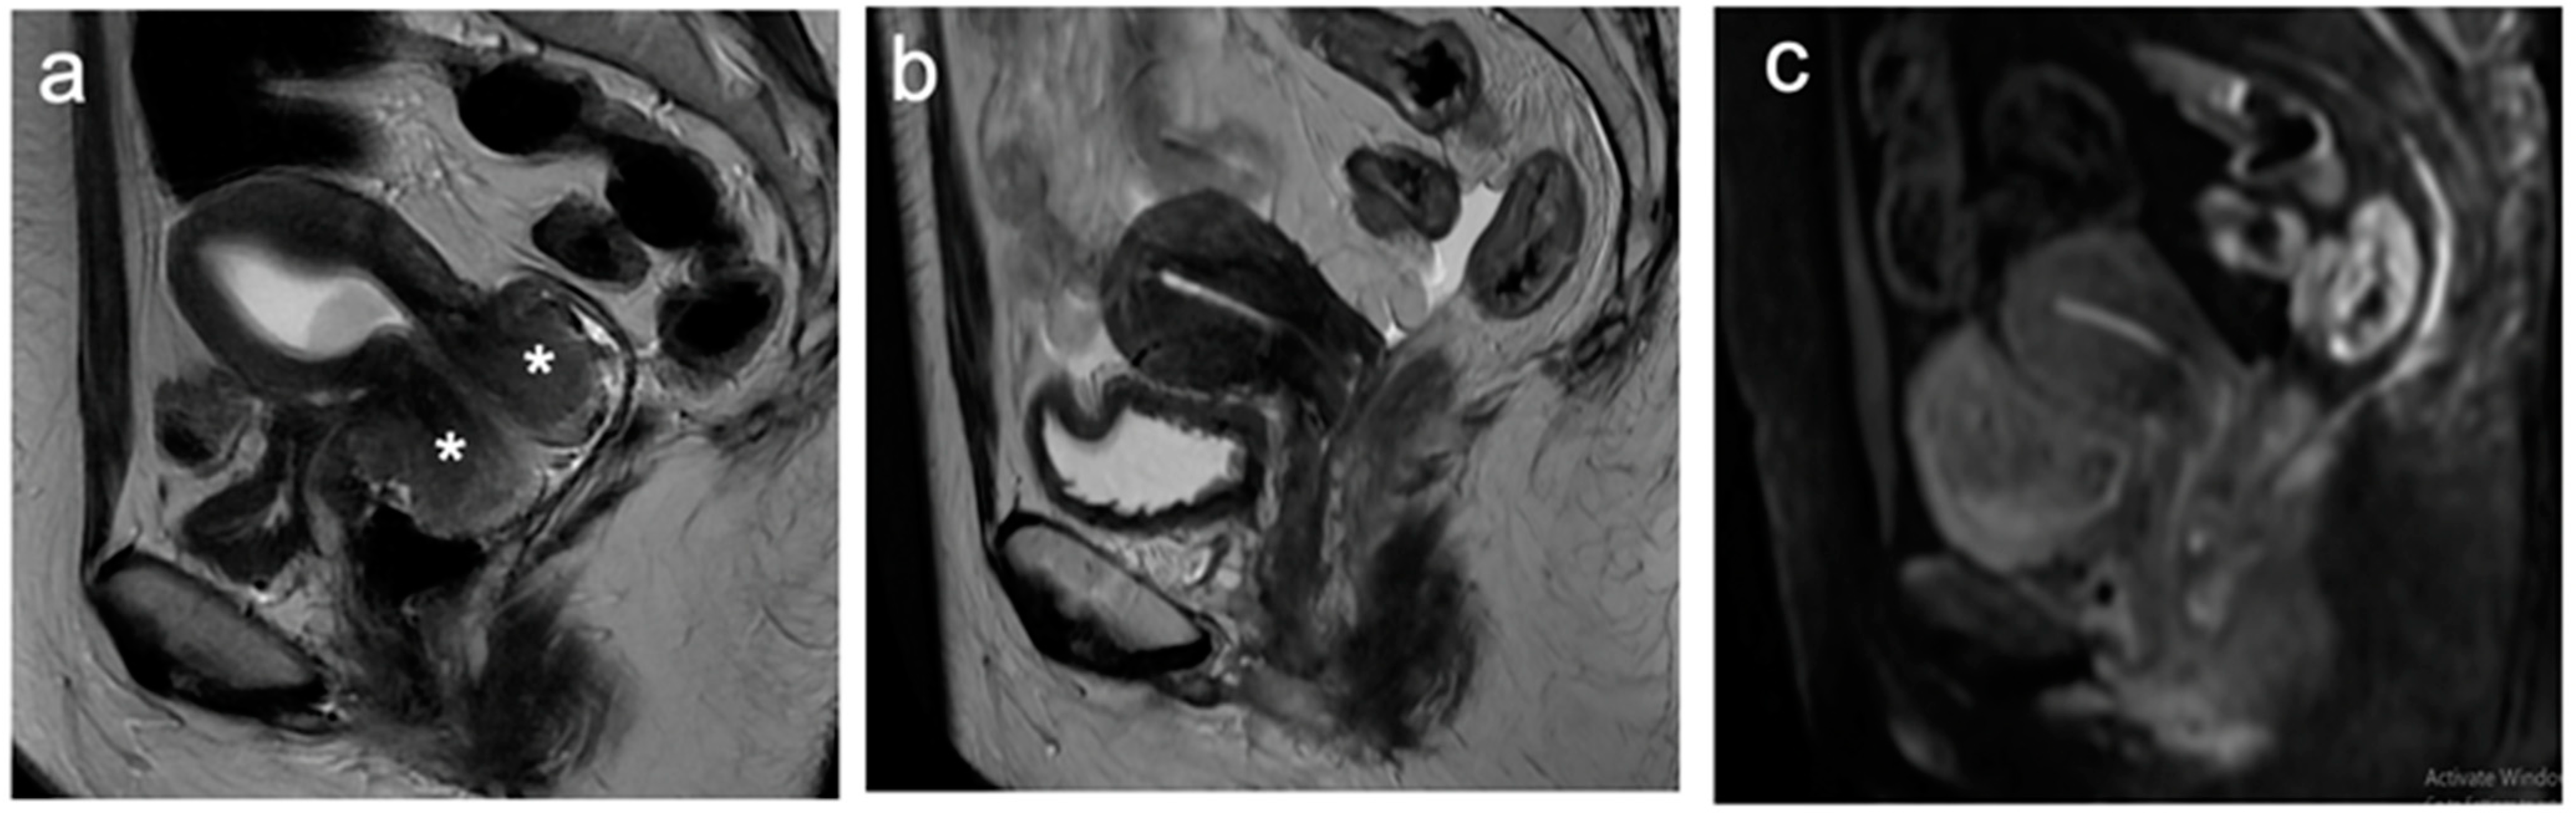

5. FIGO Stage II

6. FIGO Stage III

7. FIGO Stage IV